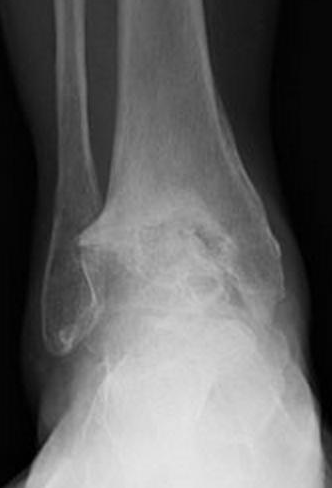

Foot & Ankle Fractures

- Overview: Traumatic injuries to the ankle, midfoot, or forefoot can lead to joint instability and arthritis if not properly treated.

- Treatment: We utilize modern fixation techniques (plates, screws, intramedullary nails, and external frames) to achieve precise alignment and promote bone healing.

- Goal: Restore anatomic alignment, maintain joint function, and allow early rehabilitation.

Post-Traumatic and Arthritic Deformities

- Overview: Previous injuries or arthritis can cause joint collapse, stiffness, and pain.

- Treatment: We offer reconstructive fusions, osteotomies, and joint replacement procedures to realign and stabilize the affected area.

- Goal: Relieve pain and enhance function.